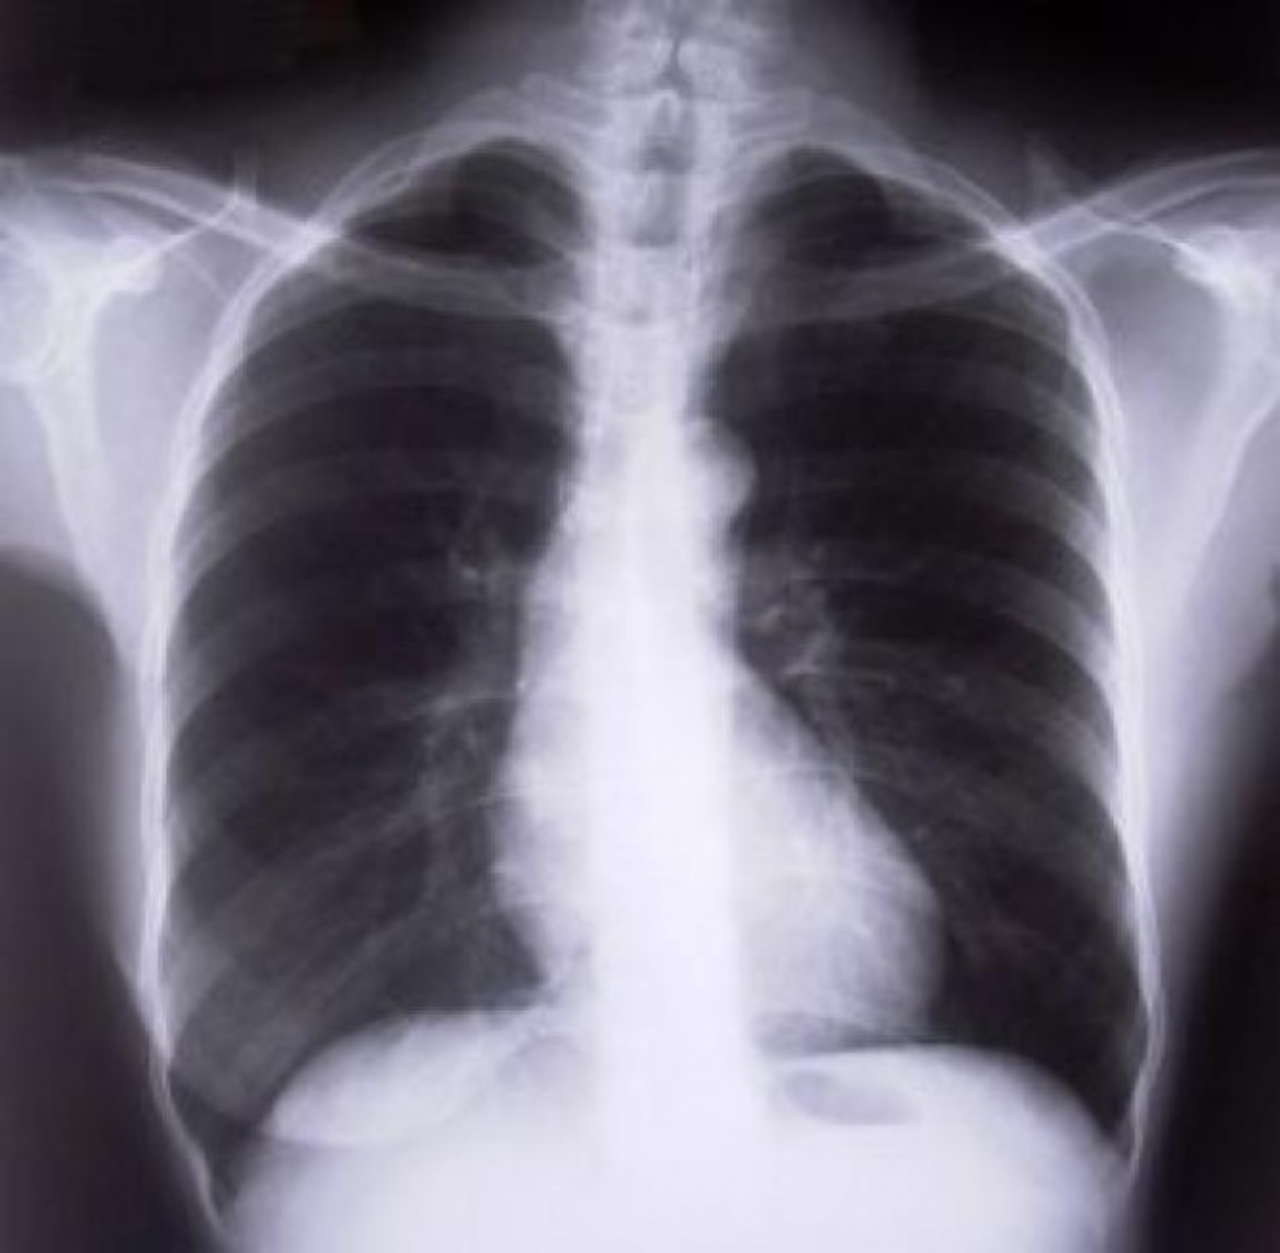

- Przede wszystkim powinien unikać wziewnych substancji szkodliwych. Po pierwsze, jeśli pali, to jak najszybciej powinien pożegnać się z nałogiem. Jeżeli wypala jakąkolwiek biomasę, to też unikać tego. Oprócz tego wykonać badania, prześwietlenie klatki piersiowej, spirometrię, no i w przypadku diagnozy i rozpoznania Przewlekłej Obturacyjnej Choroby Płuc pacjent powinien podjąć niezwłocznie leczenie – radzi lek. Med. Marzena Renflejsz

Mówi się, że POChP, to choroba palaczy. Oczywiście nikotyna i substancje smoliste, to jeden z głównych czynników ryzyka pojawienia się Przewlekłej Obturacyjnej Choroby Płuc. Jest jednak wiele innych, na które wpływu nie mamy. Takim czynnikiem jest np. praca w warunkach, gdzie narażeni jesteśmy, na różnego rodzaju chemikalia. To co powinno nas zaniepokoić, to przewlekły kaszel. Palaczom, wydaje się, że to naturalna reakcja organizmu, na ich zgubny nałóg. Nie zawsze tak jednak jest. Należy regularnie sie badać, a podstawowym sprawdzianem kondycji zdrowia w tym przypadku jest spirometria. Nieleczona POChP może doprowadzić do niewydolności oddechowej czy powikłań kardiologicznych.